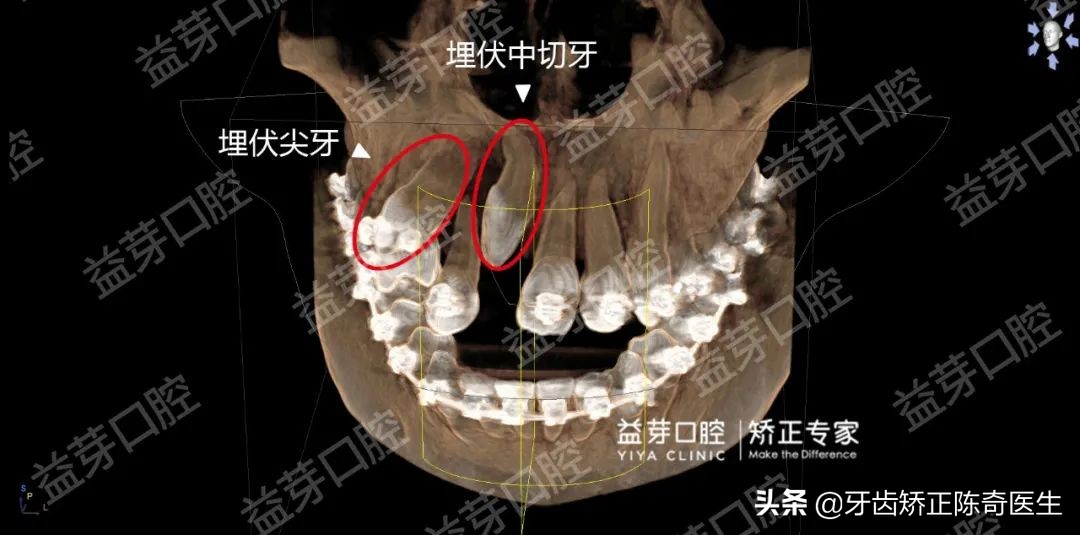

三维影像学检查显示这两颗牙齿都以错误的角度在牙槽中发育,导致无法萌出,并且将侧切牙的牙根也挤偏了。

▲三维影像学检查显示两颗埋伏牙在上颌骨里

这两颗牙是前牙埋伏阻生,临床上不算少见,但两颗牙齿一起埋伏阻生的情况就非常罕见!治疗难度也很大。同侧尖牙切牙一起阻生的情况,目前国际上能查找到的也只有李同学这一例。